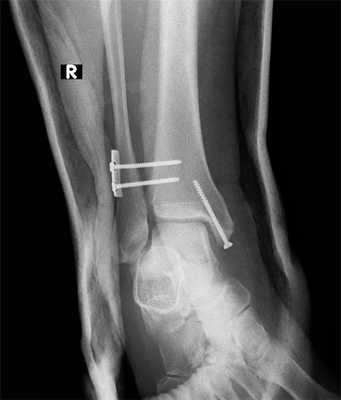

Целью операции является, прежде всего, восстановление нормальных взаимоотношений в голеностопном суставе. Если при обычном переломе лодыжек операция начинается с остеосинтеза латеральной лодыжки, то в данном случае лучше начинать, наоборот, с медиальной лодыжки, или с перелома заднего края (если он сломан и возможно выполнить его остеосинтез).

Собственно фиксация дистального межберцового синдесмоза возможна как при помощи винтов, так и при помощи пуговчатых фиксаторов. Фиксацию лучше выполнять через небольшой кусок 1\3 трубчатой пластины, чтобы распределить нагрузку на большую площадь. В противном случае существует риск последующего перелома малоберовой кости по винту, так как он будет концентрировать на себе всю нагрузку.

В случае если фиксация производится винтом или винтами, лучше использовать трёхкортикальный метод, так как он обеспечивает менее жёсткую фиксацию, и позволяет малоберцовой кости её нормальные физиологические движения в вырезке. Четырёхкортикальные винты блокируют малоберцовую кость более жёстко. И препятствуют тыльному сгибанию стопы. После начала нагрузки четырёхкортикальные винты часто ломаютя, по той же причине.

В послеоперационном периоде целесообразно «подстраховать» фиксацию первые 2 недели гипсовой лонгетной повязкой. А после снятия послеоперационных швов - циркулярной повязкой ещё на 4 недели. В повязке допустима дозированная нагрузка - весом конечности.

Во время операции необходимо произвести ревизию межберцовой щели из того же латерального доступа. Это необходимо: во-первых для контроля адекватного устранения смещения, во-вторых, для устранения интерпозиции связок образующих ДМБС и небольших костных фрагментов в малоберцовой вырезке, в-третьих для предупреждения мальпозиции малоберцовой кости при наложении костной цапки и при установке синдесмозных винтов.

Крайне важно контролировать позицию малоберцовой кости и на истинном боковом снимке, так как наиболее частой ошибкой является её трансляция кпереди при установке костной цапки.

При соблюдении всех вышеперечисленных нюансов, возможно адекватное устранение подвывиха, и возвращение малоберцовой кости в нормальную анатомическую позицию, что в конечном счёте обеспечивает максимально возможное восстановление функции.